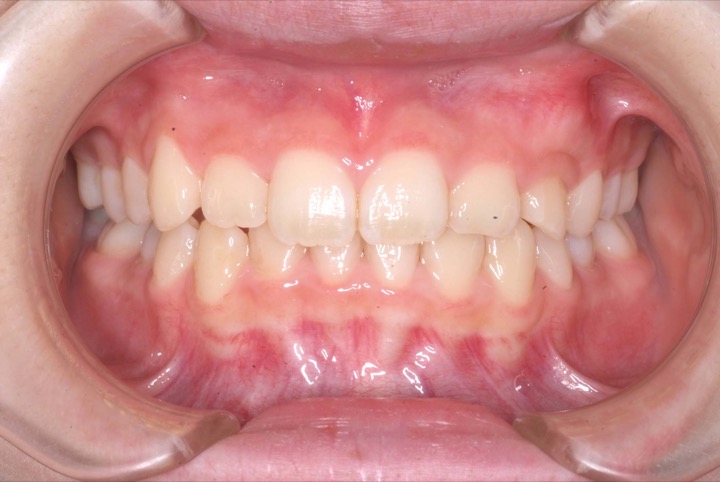

初診時年齢9才の女子で上下顎前歯の部の乱ぐいを気にして来院されました。

検査の結果、叢生と過蓋咬合を伴うアングルⅠ級不正咬合と診断しました。

前期治療は、非抜歯の上、マウスピース型矯正装置(インビサライン・ファースト)で行いました。その後、歯列矯正用咬合誘導装置(マイオブレース)で舌位の改善を行いました。治療期間は5年1ヶ月でした。通院回数:37回。